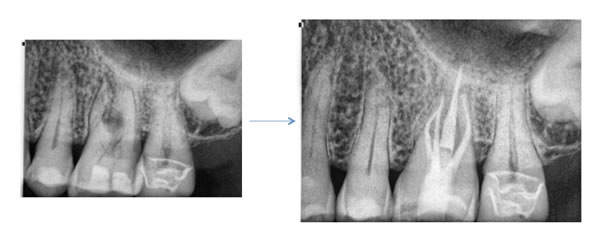

Case by Dr. Michael Brown

The image below is from an endodontic textbook published in the early nineties. Their ideal access is outlined for a maxillary first molar. In reality, the mesial lingual canal is usually mesial to where the older text books indicate. In second molars the second mesial canal is usually further palatal than is found in maxillary first molars.

Do they meet? Many times the ML canal will join the MB. However, contrary to what we often hear, even if the canals meet, the untreated ML canal can adversely affect the outcome or long term success of the endodontic treatment. Finding both canals is crucial to complete endodontics on a maxillary first molar.